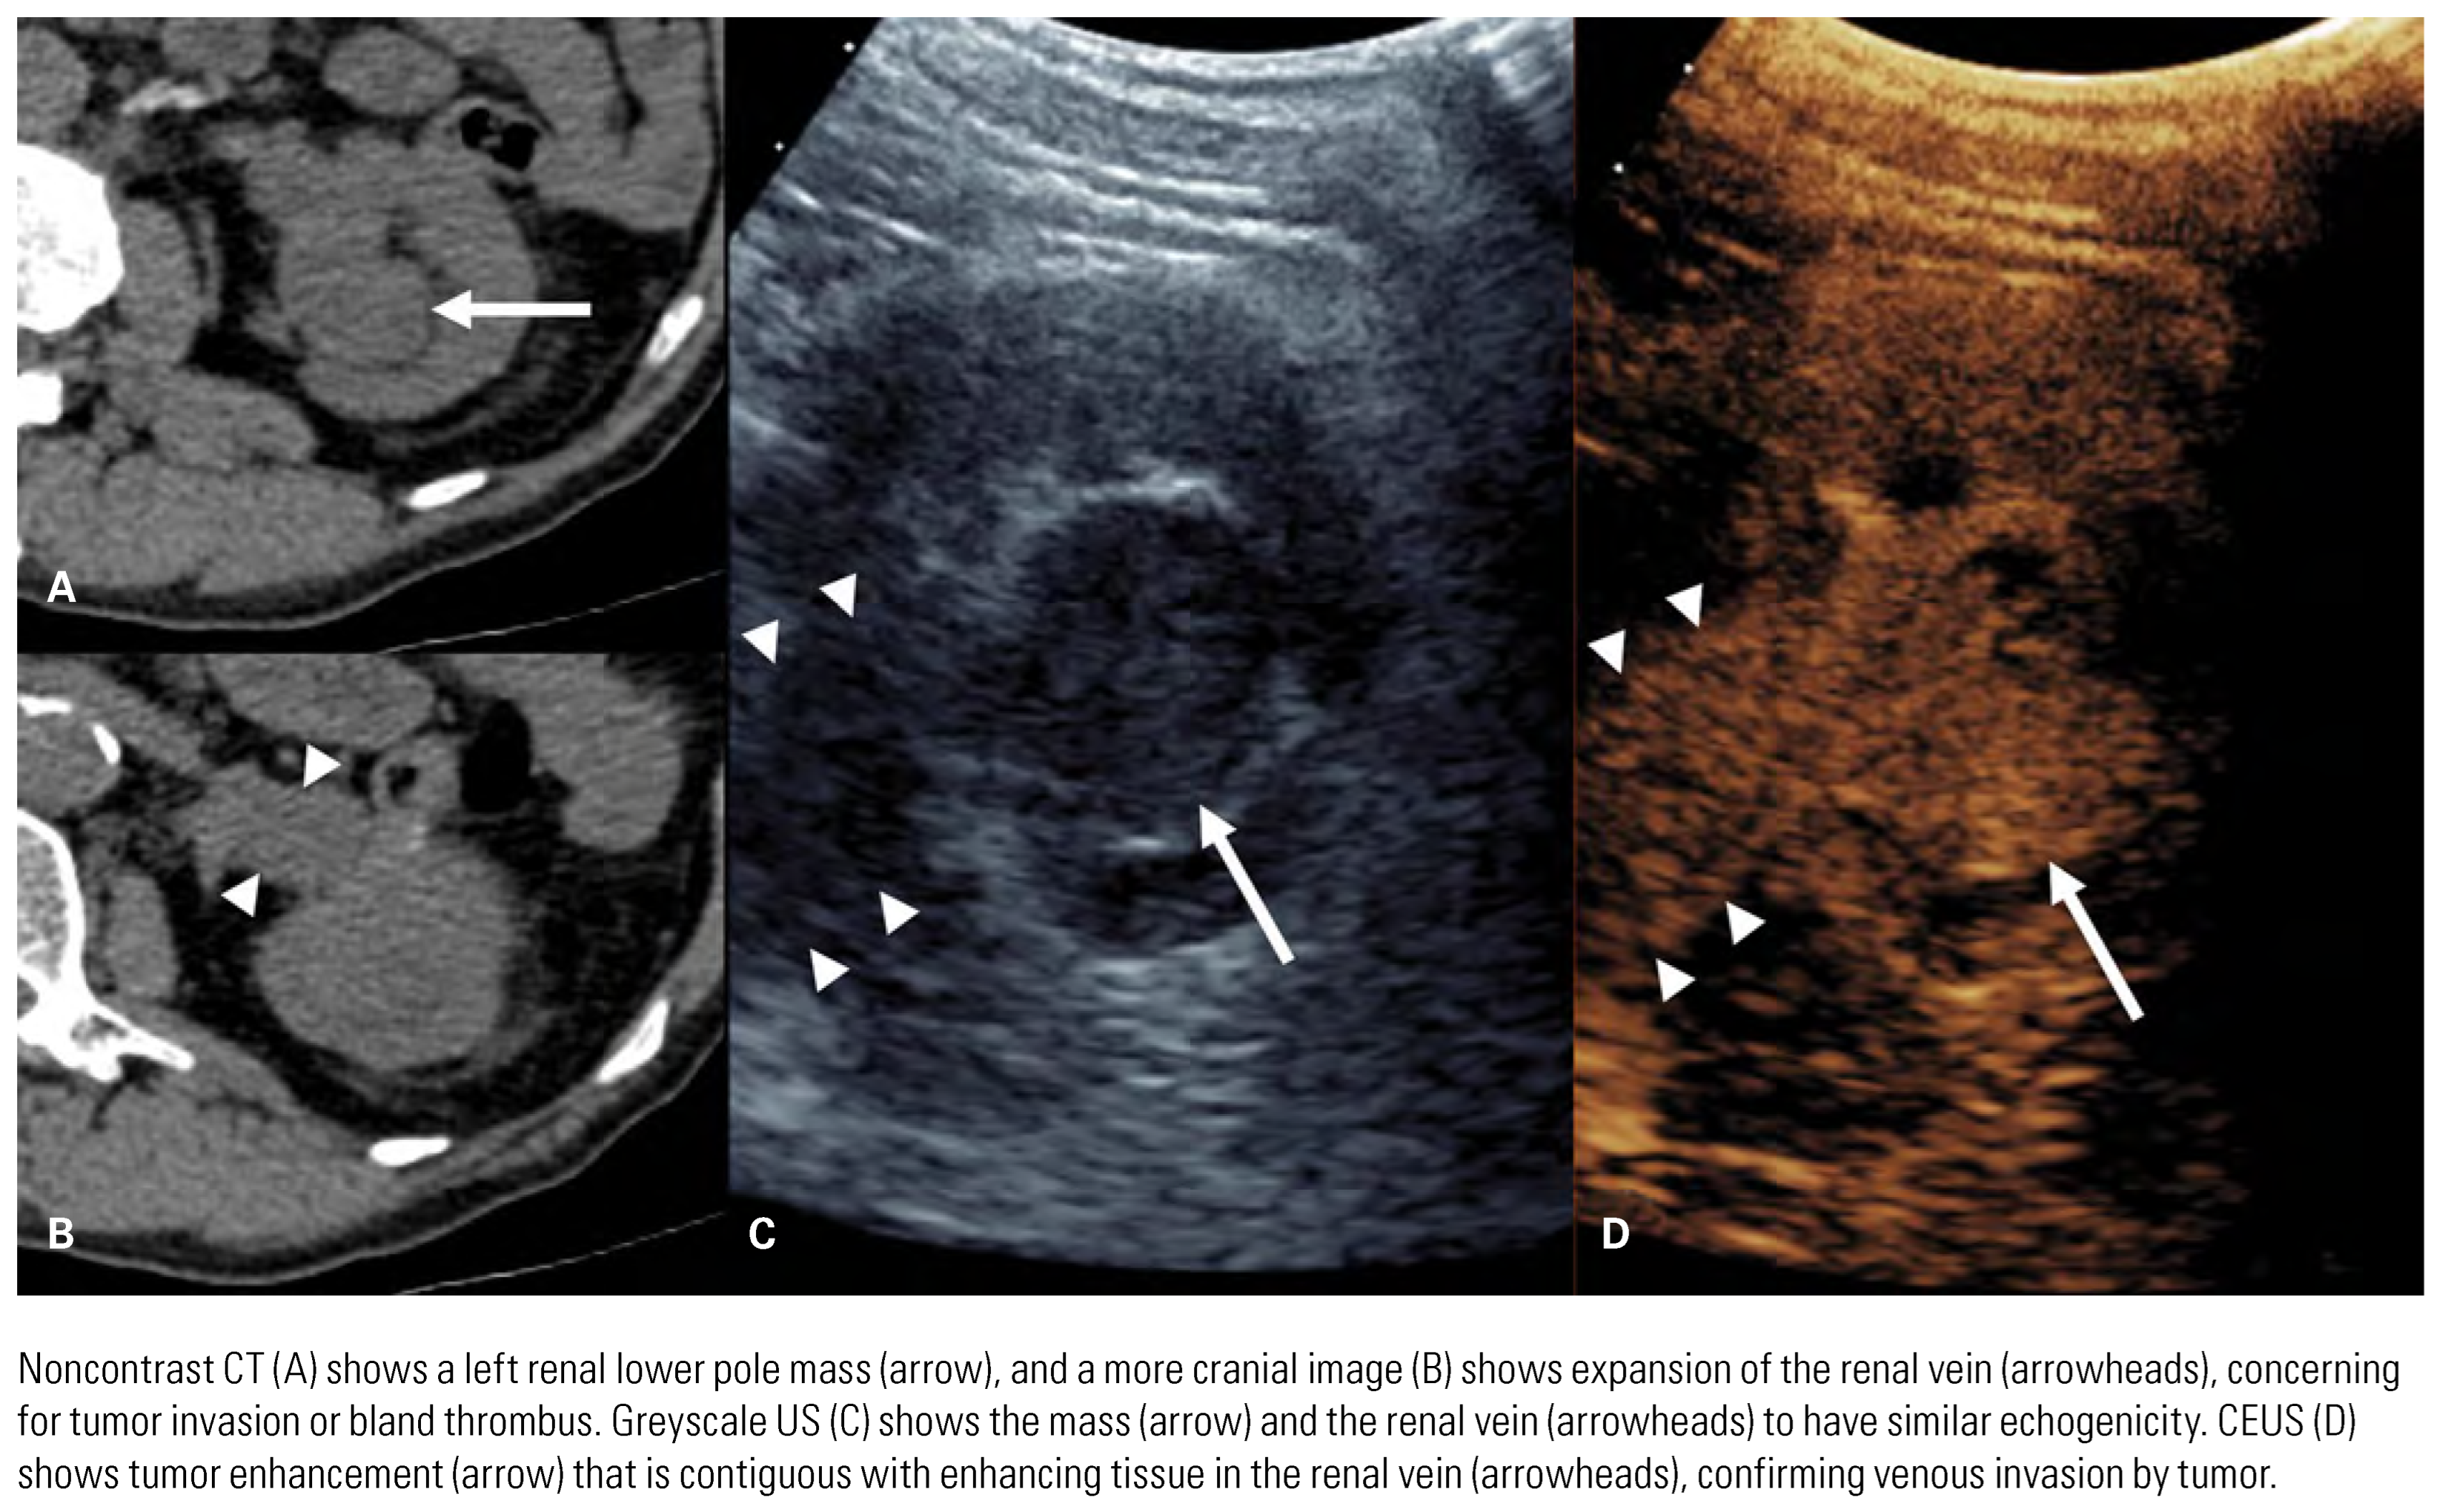

Evaluation of Primary Tumor